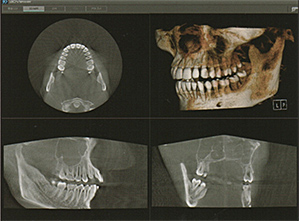

被ばく線量の少ない高画質な歯科CT診断装置で、安心して撮影していただけます。

CT画像は、歯根の治療、歯周病治療、口腔外科のなど様々な角度から精密な診断が行え、安全で精度の高い治療に役立てます。